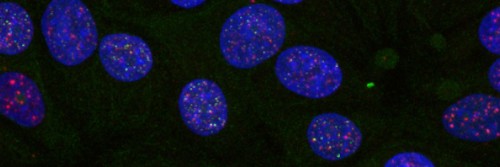

Our researchers have pioneered the use of imaging methods such as PET/CT, MRI, and live microscopy to observe and measure biological processes over time. By highlighting living cells or tissues with specific agents, we use these technologies to aid laboratory investigations into the root causes of cancer and to develop innovative approaches to improve diagnosis and treatment.